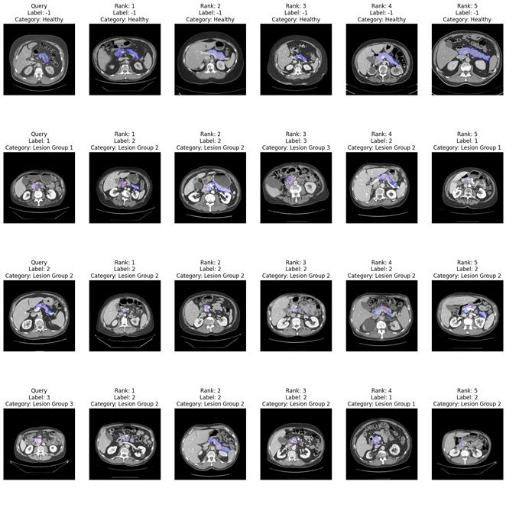

Figure 2 presents four different test queries from the Pancreas test set and the top 5 nearest neighbors retrieved by the volume-based search method. In each row, the first image is the query, followed by the retrieved images ranked by similarity. The visual overlays help in assessing retrieval accuracy;

- Blue indicates the pancreas organ boundaries, and

- Red highlights the mark regions corresponding to the pancreas tumor.

| Figure 2: Top 5 results for different queries from the Pancreas test set |